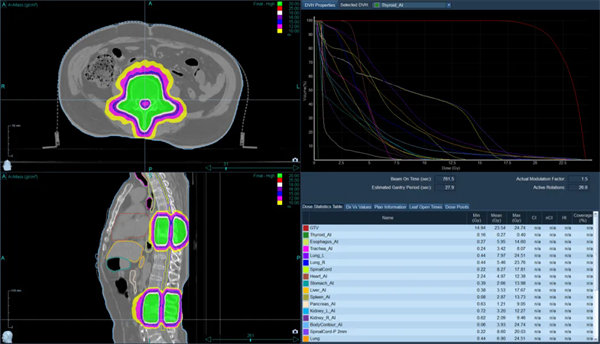

TOMO劑量分布均勻,適型度高

針對患者的病情,血液腫瘤風濕免疫內科副主任朱暉和放射治療科張世衡副主任醫師反復討論,最終確定長范圍、多病灶靶區的治療方案。由于患者及家屬對放射治療止痛效果的疑慮,科室反復多次和患者及家屬溝通:“張師傅,您放心吧,我們醫院的TOMO加速器是目前世界上最先進的放療機器之一,它的優點就是:TOMO有效治療范圍更大,最長可40CM*135CM,對于多發病灶可以在同一個定位區間內同時治療,正是TOMO這樣的特殊設計和功能,照射腫瘤的部位更精準、對周圍正常器官副作用小,而且每次治療之前都有CT圖像引導,可以根據病灶情況實時調整勾畫靶區,請您相信我們”。經過一番耐心地解釋說明,張師傅及家屬慢慢打消了顧慮,積極配合治療。在經過反復確認靶區、劑量及危及器官限值,科室討論后,一致認可此次放射治療的安全性和可實施性,放射治療科團隊加班加點,在兩天之內完成了制模,定位,靶區勾畫,計劃設計驗證,用最短的時間給張師傅安排了放射治療。血液腫瘤風濕免疫內科及放療主管醫生著重觀察患者對放療的反應,密切監測血常規、生化等指標,結合對癥支持治療,做好保駕護航。僅僅經過2次放療,張師傅腰背的癥狀就有了明顯的改善,晚上能安穩睡到天亮,直至5次放療結束患者未出現不可耐受的副作用。

肋骨、胸椎、腰椎轉移灶的長靶區照射(紅色區域)

患者及家人喜悅的表情給了我們最大的肯定。TOMO放療設備作為目前世界上尖端的放射治療設備之一,具有高度的精準性和適應性,能夠顯著提高腫瘤治療的療效,長靶區照射一次解決問題。通過引入TOMO放療,開啟了腫瘤多學科綜合診療模式,提升了我院在腫瘤診療、疑難病例診療能力等方面的綜合實力,更好地滿足患者對高質量醫療服務的需求,同時,也將推動醫院在腫瘤防治事業上的高質量發展。